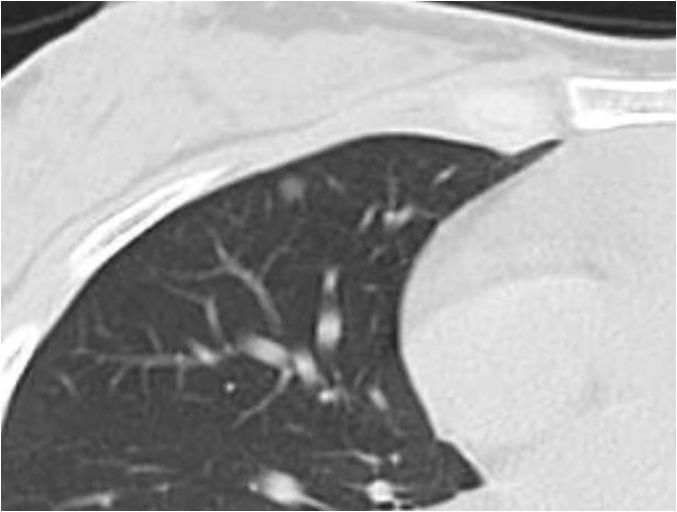

Chest CT images, showing groundglass nodule on the right upper lobe Glass Nodules Definition It can be from other diseases, unrelated to. lung nodules are small growths in your lungs, less than 30 millimeters in diameter. These areas show increased density inside. ground glass opacity (ggo) refers to the hazy gray areas that can show up in ct scans of the lungs. Many nodules aren’t cancerous, but the risk. “a nodule. Glass Nodules Definition.